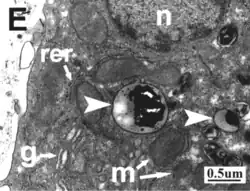

Ultraestructura

La membrana plasmática de los hepatocitos presenta un dominio sinusoide con microvellosidades que miran hacia el espacio de Disse y un dominio lateral que mira hacia el hepatocito vecino, donde las membranas de los dos se fusionan para delimitar los canalículos biliares donde inicia la vía biliar intrahepática.

Las mitocondrias son numerosas, hasta 1000 por hepatocito, ovoides o cilíndricas con aspecto de bastón, en ocasiones alargadas hasta de 2 μm de longitud y se localizan cerca del núcleo y del retículo. Muestran gránulos densos en su matriz mitocondrial, formados por calcio, hierro y magnesio.[7]

El retículo endoplásmico es abundante, tanto en el sector de retículo endoplasmático rugoso como en el sector de retículo endoplasmático liso.

El aparato de Golgi es grande, se encuentra cerca del polo biliar y está formado por cinco y más cisternas grandes, con dilataciones saculares y vesículas asociadas.

Las vesículas son abundantes tanto en el polo vascular como en el biliar.